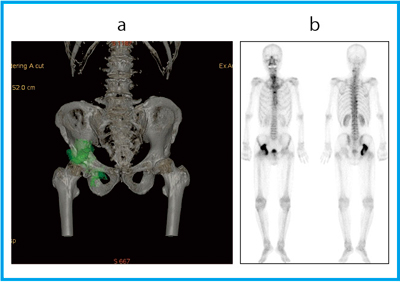

全身骨シンチグラフィ 乳癌 肺癌 前立腺癌等の骨転移病巣の検出

全身骨シンチグラフィ 乳癌 肺癌 前立腺癌等の骨転移病巣の検出

骨シンチグラフィによる骨転移の診断 Bone Scan Ct Mri画像診断